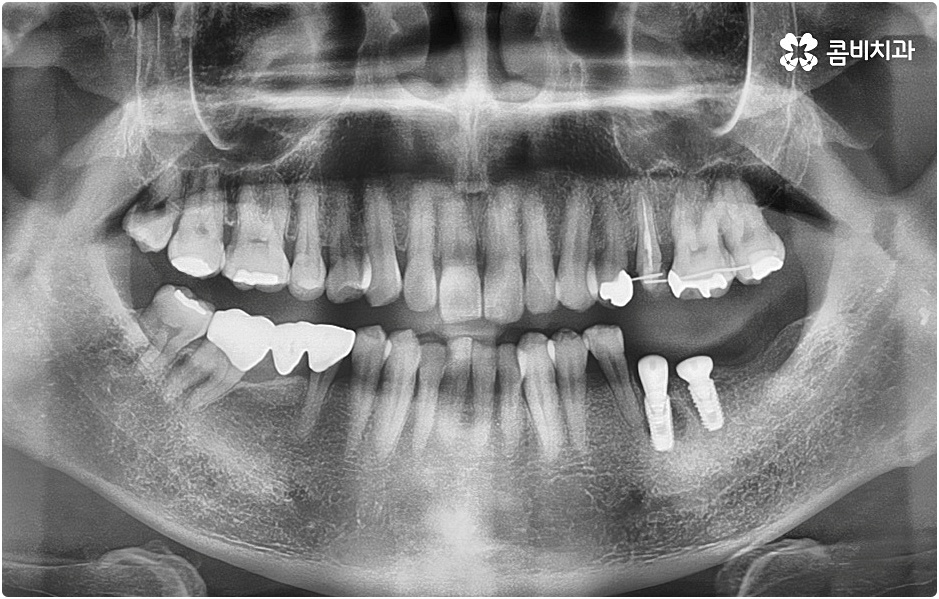

임플란트 시술을 받을 때 치아를 상실한 원인이 무엇인지, 상실하고 나서 그대로 둔 시간이 얼마나 되는지, 현재 치아나 잇몸 등 구강 내부 상황이 어떤지 등등을 먼저 꼼꼼하게 파악할 필요가 있는데요. 예를 들어 20대임플란트 를 받게 된 원인이 사고와 같은 외부 충격으로 인한 것이고 시간이 많이 흐르지 않은데다 다른 구강 질환 (충치나 치주 질환) 이 크게 문제가 되지 않는 상황이라면 젊은 나이이기 때문에 바탕이 되는 잇몸뼈 건강이 비교적 양호할 것이라고 예상할 수 있으며 이런 경우 즉시 임플란트 방식을 검토해 볼 수 있어요. 면밀한 정밀 검사 후 가능하다는 의료진의 진단이 내려진다면 당일에 인공 치근을 심고 임시 크라운까지 올려 바로 사용할 수 있는 즉시 임플란트 방식을 통해 보다 빠르고 간편하게 수복을 할 수 있습니다.

그러나 나이가 젊다고 해도 만약 치아를 상실한 원인이 심각한 구강 질환으로 인한 것이거나 치아를 잃고 나서 오랜 시간 방치를 하였거나 평상시에 당뇨 또는 고혈압 등을 앓고 있었다면 환자분의 잇몸뼈 건강이 양호하지 않을 수 있으며 그런 경우에는 즉시 임플란트 시술을 받을 수 없고 먼저 뼈이식 과정을 통해서 잇몸뼈를 보충해 준 다음 20대임플란트 식립을 진행하는 것이 정확도와 지속성을 높여주는 방법이라고 할 수 있어요.

그러나 언급했던 것처럼 잇몸뼈 상태에 대해서 먼저 체크해 봐야 하기 때문에 누구나 받을 수 있는 치료 과정은 아니라는 점을 분명히 알아두실 필요가 있습니다. 이렇게 잇몸뼈를 보충해야 하는 상황 뿐 아니라 충치 또는 치주 질환을 먼저 깨끗하게 치료해야 하는 상황, 상악동까지의 거리가 너무 짧아서 거상술을 통해 혹시 모를 천공과 염증을 방지해야 하는 상황 등 여러 가지 선치료가 필요한 케이스들이 있을 수 있기 때문에 먼저 환자분들의 상황을 자세하게 파악하기 위해서 꼼꼼한 검진을 해 볼 필요가 있으므로 3D CT 등 정밀 검진 장비 보유 여부가 필수적이라고 말씀드린 거예요.